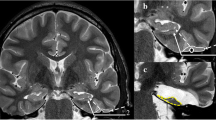

Once the ventricle was cannulated, a 12-mm diameter tubular retractor was introduced to facilitate visualization and maneuverability during the intraventricular stage of the procedure. Upon fixation of the retractor, a 30° lens endoscope (1488 HD System, Stryker, Kalamazoo, USA) was introduced to the temporal horn. After accurately identifying the main structures within the ipsilateral temporal horn, we measured and assessed cortical landmarks to guide the entry into the ventricle. In addition, the transparenchymal distance and the trajectory lengths to intraventricular landmarks were measured (Fig. 2A, B).

A Endoscopic intraventricular image after performing our anterior endoscopic approach on the right temporal horn using a 30° lens, showing the head of the hippocampus HH, head of the hippocampus; CP, choroid plexus; LWV, lateral wall of the ventricle. B Endoscopic intraventricular image after performing our anterior endoscopic approach on the right temporal horn using a 30° lens, showing the body of the hippocampus. BH, body of the hippocampus; CP, choroid plexus; LWV, lateral wall of the ventricle; CE, collateral eminence; CG, choroid glomus; LVS, lateral ventricular sulcus

Intraventricular image after performing the ATE-SelAH on a right temporal horn. The arachnoid of the ambient cistern has been removed for a good exposure of the main structures CP, choroid plexus; BVR, basal vein of Rosenthal; HV, hippocampal vessels; M, midbrain; P2A, P2A segment of the posterior cerebral artery; ET, edge of the tentorium; ITA, inferior temporal arteries; white asterisk: quadrigeminal cistern; white dot: crural cistern

Our entry point into the ventricle through the aMTG to reach the amygdala was located between the UF and anterior to the Meyer’s loop, optic radiations, and IFOF. Our approach went through a subcortical window located in the aMTG and formed anteriorly by the posterior part of the UF, posteriorly by the L-Arc, Meyer’s loop, and the IFOF, and inferiorly by the ILF (Fig. 4).

Picture showing the entry point of the endoscope into the ventricular system through the subcortical window. The subcortical window (yellow) is located in the anterior middle temporal gyrus, formed anteriorly by the posterior part of the UF (blue), posteriorly by Meyer’s loop, optic radiations (red) and IFOF, posteriorly and superiorly by the L-Arc and inferiorly by the ILF. Our trajectory was confirmed by neuronavigation UF, uncinate fasciculus; ML, Meyer’s loop; OR, optic radiations; AC, anterior commissure